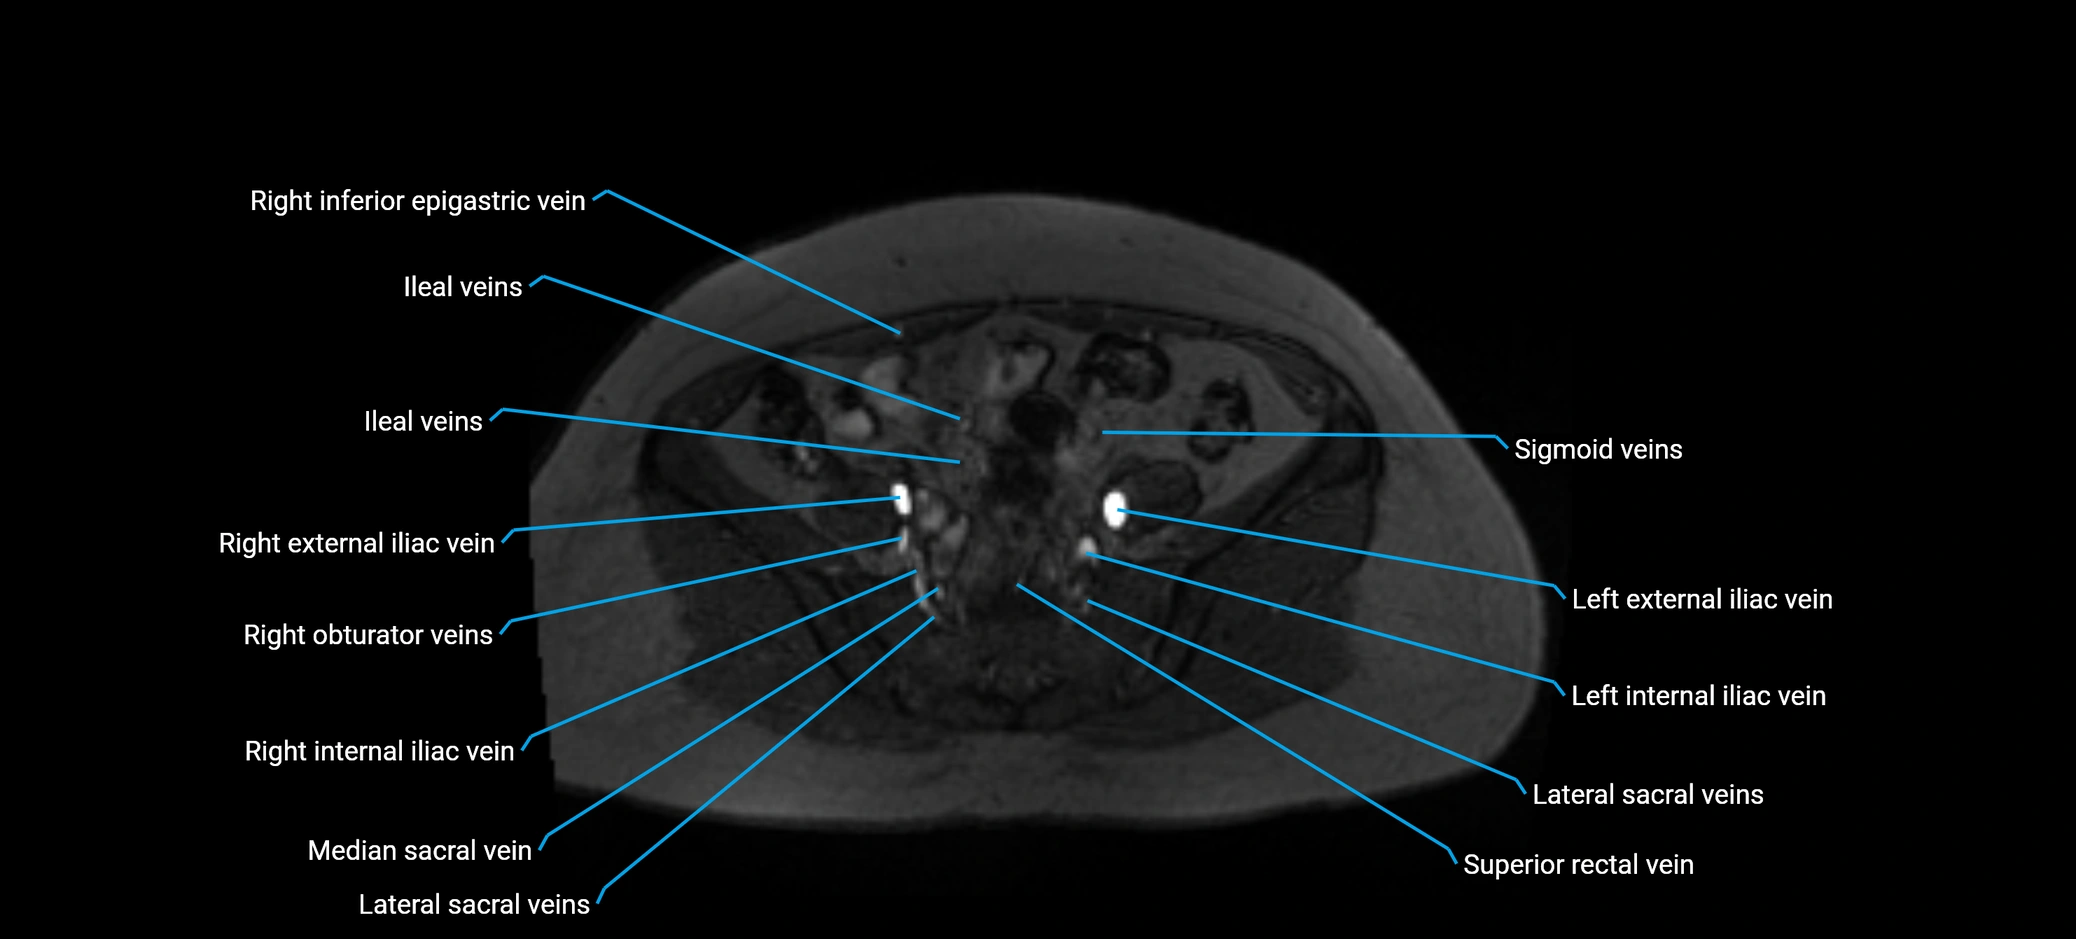

MRI image

image